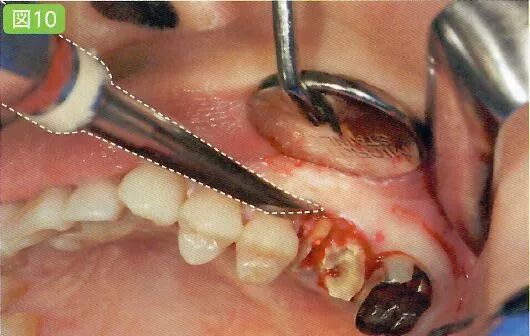

牙齿脱臼

剥离同样如此,无论向几个方向插入牙挺。口腔卫生士最好事先预想一下会插入哪几个部分再使用吸唾器吸引。

牙挺拔牙时,牙槽骨和牙齿之间插入牙挺引起的牙齿脱臼

插入牙挺部位的视野一定要清晰

(插入前将牙挺置于牙槽骨和牙齿之间,插入时优先插入牙挺尖端)

确认完成缝合的部位是否有出血。由于牙周膜腔部分会出血,用吸唾器吸收牙槽骨和牙根之间的交界处(图10)。此外,向牙挺施加力的时候会出血,一定要使用吸唾器不厌其烦地吸引牙挺尖端部分血。

吸引牙周膜腔的出血时,一定要保证主治医生的的视野清晰。